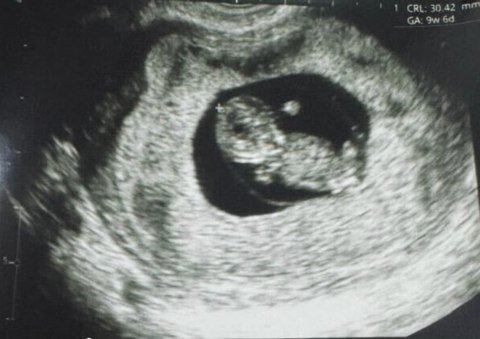

Репродуктивна медицина зробила історичний крок уперед: у Перу вперше народилася дитина, зачата за допомогою новітньої технології Fertilo, яка використовує стовбурові клітини для дозрівання яйцеклітини поза організмом.

Це відкриття стало можливим завдяки роботі біотехнологічної компанії Gameto, повідомляє New Atlas, передає Час Пік.

На відміну від традиційного екстракорпорального запліднення (ЕКЗ), Fertilo застосовує інноваційний підхід. Замість стимуляції яєчників гормональними ін’єкціями, використовуються опорні клітини яєчників (OSC), вирощені зі стовбурових клітин. Ці клітини поєднують із незрілими яйцеклітинами, а в лабораторії імітують природний процес їх дозрівання.